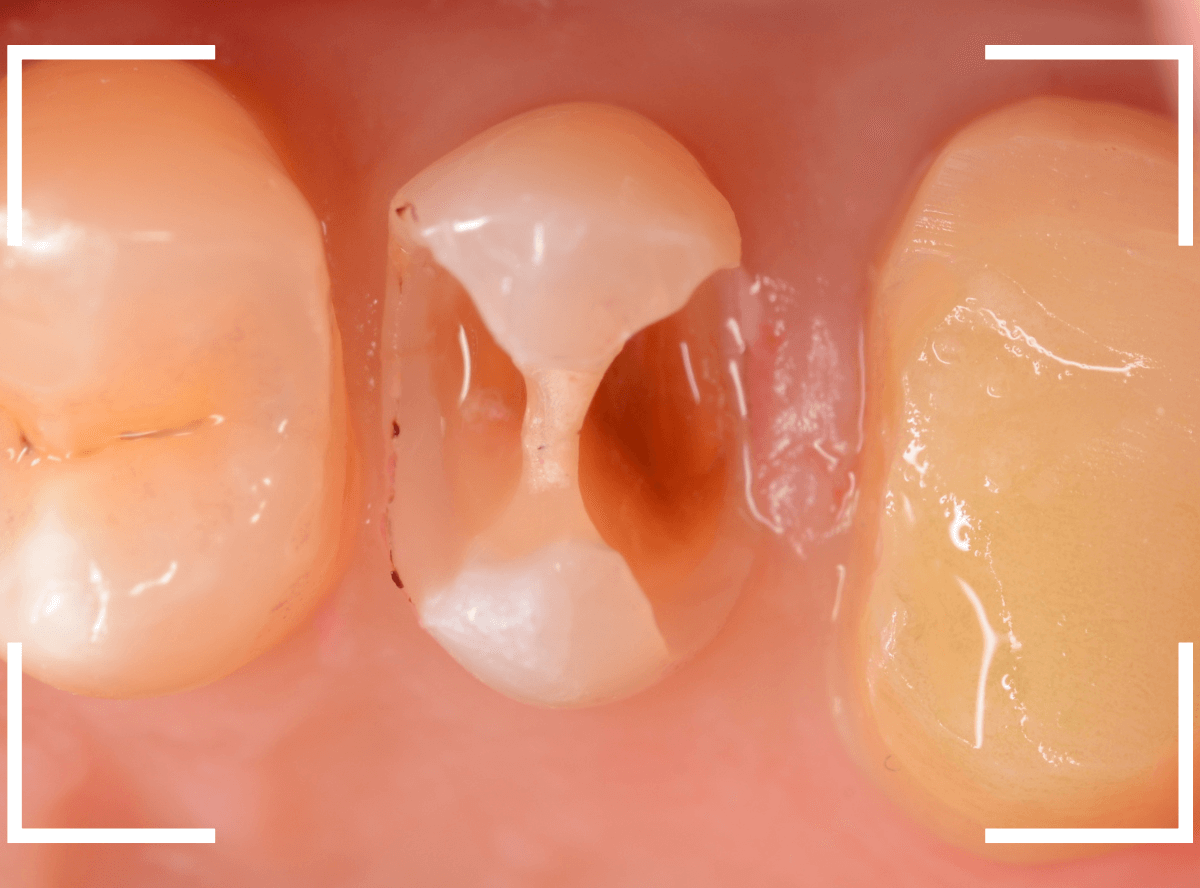

手前の歯のつめ物も外します。

こちらもお薬が入っていますが、外して中を調べます。

こちらは中も問題なかったです。

奥歯は歯に優しいファイバー・コアで再製し、型取りします。

模型上で精密に製作します。

set後の写真です。

患者さんにも満足していただける仕上がりになりました。